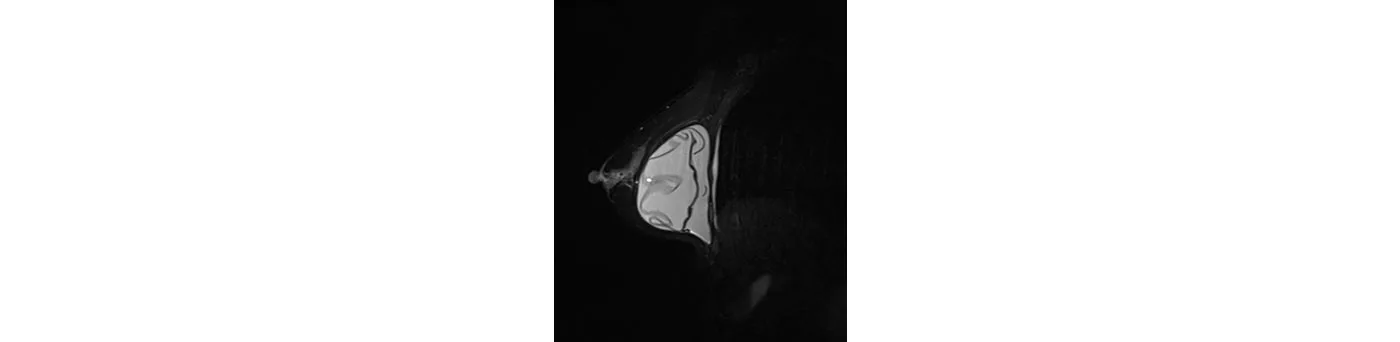

Người bệnh nữ, 51 tuổi, sau đặt túi ngực 10 năm, đi khám định kì, chụp cộng hưởng từ phát hiện rách trong bao hoàn toàn túi ngực bên phải.